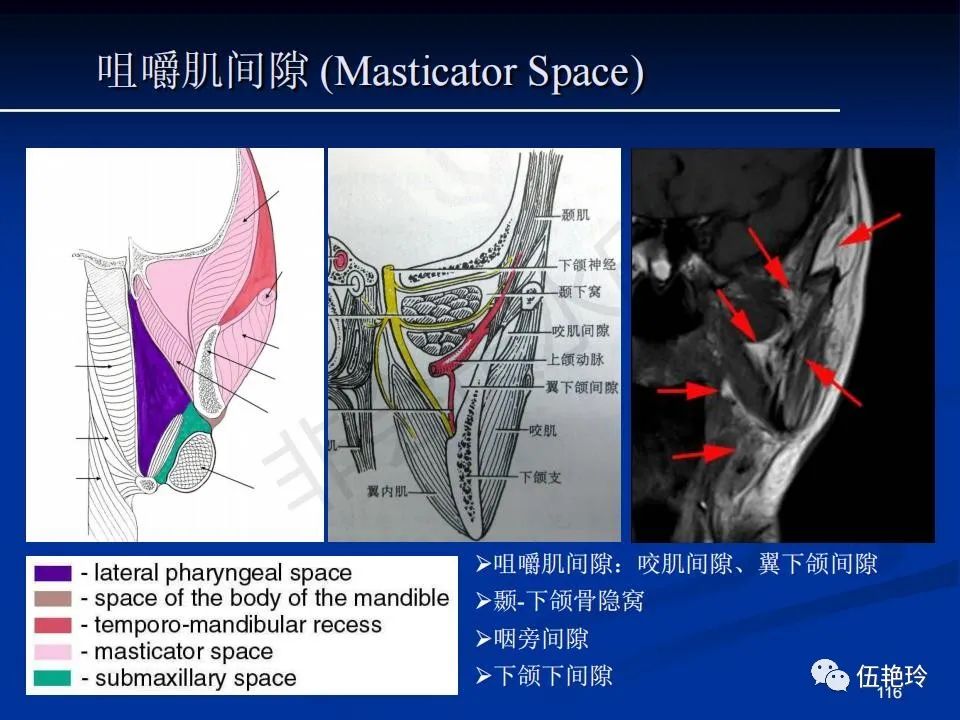

颞下窝与咀嚼肌间隙

2.31 向上颅内:①鼻咽顶壁→破裂孔(岩尖、斜坡)→蝶窦、海绵窦;②鼻咽顶壁→蝶骨基底部→蝶窦、海绵窦;③鼻咽侧壁→茎突前间隙→蝶骨大翼(卵圆孔)→海绵窦;④鼻咽侧壁→茎突前间隙→翼腭窝→ 颞下窝;⑤鼻咽前壁→鼻腔→翼突、翼腭窝→眶下裂→眶尖→海绵窦;⑥鼻咽前壁→鼻腔→上颌窦、筛窦;